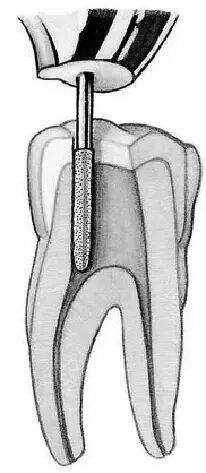

5. 根管最狭窄处距根尖0.5-lmm,是清理、成形和充填根管的末端,但随着年龄的增长这个距离会增大,需要引起我们的注意。结合下面的6,可以有一个图来表示,这个图看的时候需要静下心来,要不半天反应不过来。

6. 在考虑根管预备和充填的位置时,应将牙本骨质界至根尖孔的距离以及根尖孔至根尖端的距离两个因素同时考虑进去,以避免超出造成根尖周组织的损伤。

口腔H锉怎么消毒牙科医生必须看看----经典根管治疗总结_https://www.jmylbn.com_新闻资讯_第3张

看上图,我们rct时恰填的位置应该是(4)-牙本质骨质界,随着年龄的增长,这个位置距离X线片上根尖位置越来越大,这也就是为什么现在并无法定出一个根充恰填的X片上的标准,站在不同的位置,视角是不一样的。读到这想起了乳牙龋坏的好发牙位在《牙体牙髓病学》和《儿童牙病学》完全的不同,也是一样的原因-视角。